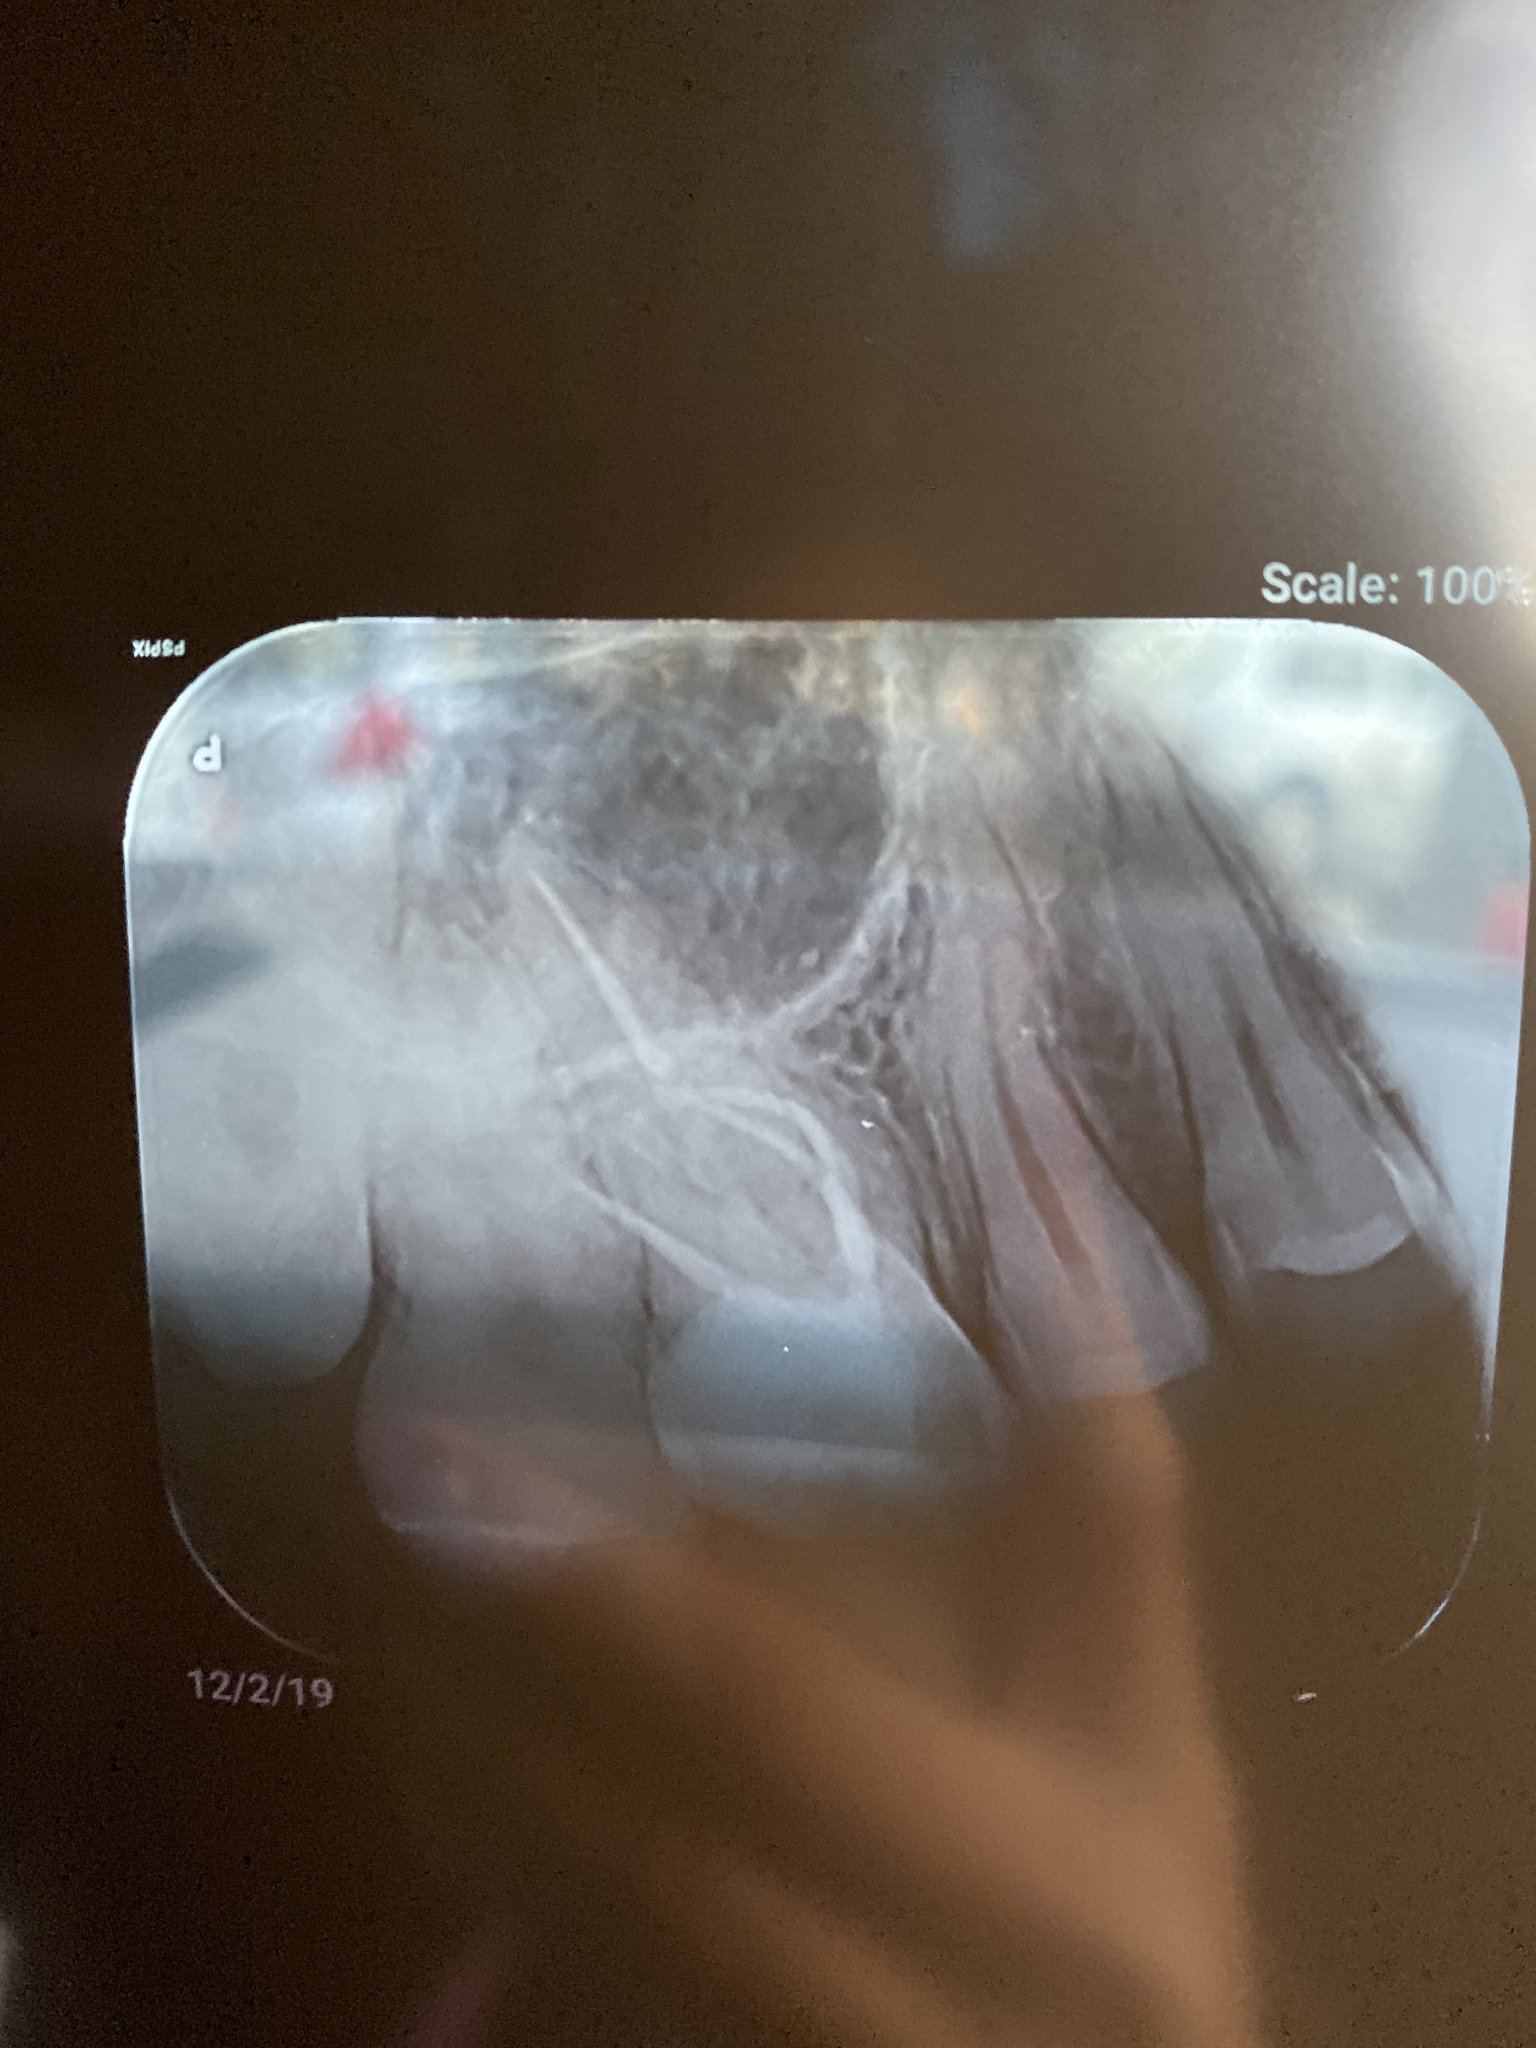

Здравейте , търся помощ , защото съм много притеснена , преди месец и половина симпоръчах торта орехова , в която имаше костилка , при сдъвкване ми се отчупи пломба на горен шести зъб в дясно , след седмица започна болка и при направена снимка се оказа че пломбата е много близо до пулпата и зъболекаря го умъртви , месец вече след умъртвяването имам болка само при дъвчене , ходех три пъти при него каза че всичко е наред , каналите били запълнени идеално и няма причина за болка , изпили ми зъба да няма контакт с долния , но и това не помогна и болката си остава , моля ако някой е имал подобен проблем да изкаже мнение , Благодаря ! ( прикачвам снимка )